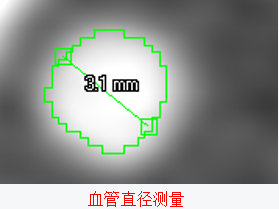

图像测量是指对图像中目标或区域的特征进行测量,包括图像的灰度特征、纹理特征和几何特征。

定量分析腔体、肿瘤的体积,血管的直径,三维区域的平均密度;

二维基础上的距离、面积、角度和统计分布等测量;

三维基础上的空间距离、曲线长度、表面积和体积等测量;

鉴别有无病变、病灶的大小和空间方位,提供定性诊断及预测的参考依据。

直径(面积)测量法:

将狭窄处官腔直径(面积)与相邻近端和远端正常官腔直径作比较,得出比值。